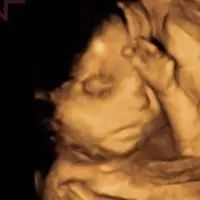

3月18日,伊能静在微博晒出肚中宝宝的四维图,并坦言医生有所叮嘱:高龄妈妈早产的可能性比较高,让她六月中下旬就要有所准备. 她还透露,丈夫秦昊看着宝宝的四维图笑了一晚,言语中满是幸福甜蜜. 网友留言:“祝福宝宝一切都好,妈妈加油!”“期待小秦秦的到来!”“心情美...